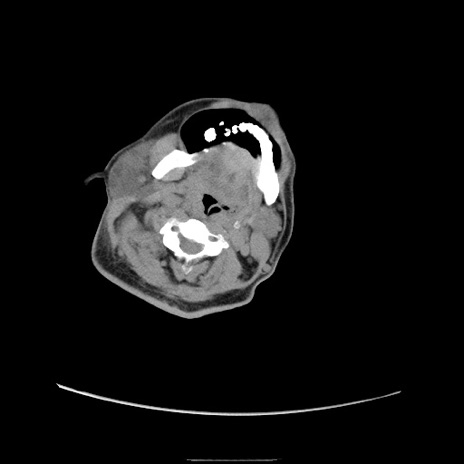

症例22(横断像)

【症例】50歳代男性

【主訴】腹痛

【現病歴】AVMからの被殻出血のため回復期リハ病棟入院中。 本日午後3時頃急に下腹部痛が出現した。

【既往歴】AVM、被殻出血、虫垂炎、高血圧

【身体所見】意識晴明、左半身不全麻痺、会話の理解は良好、36.5°C、腹部:膨隆、全体に板状硬、下腹部正中に圧痛点あり、反跳痛-、筋性防御不明、右下腹部にope scar

【データ】WBC 9400、CRP 0.06